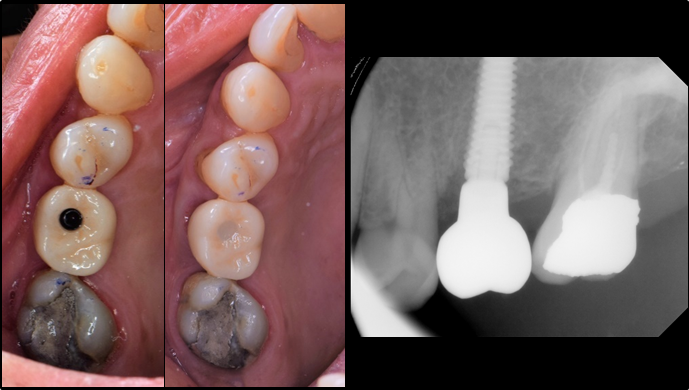

“Prefabricated provisional restorations can serve as custom healing abutments in case of insufficient initial stability for one-day implants. ”

Clinical case: Immediate implant placement using R2GATE Guide & custom healing abutment

- Courtesy of Dr. Sam Omar, Egypt -

Keywords

Dr. Dr. Sam Omar,Digital Guided Surgery,Digital Digital Guided Surgery,Digital ONE-DAY Implant,Maxillary Posterior,#16,Guided surgery,Loading,Flapless,AnyRidge,R2GATE,MEGA ISQ,R2GATE Full surgical kit